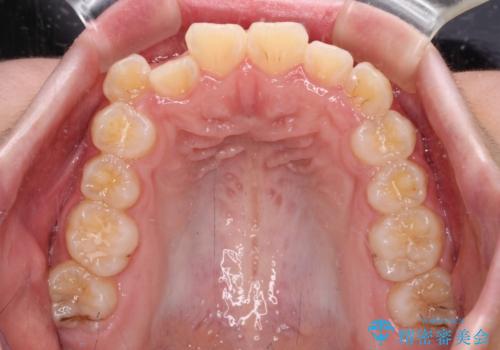

舌の突出癖により上下前歯は接触できず、更には前方に押し出されて出っ歯になっている状態でした。

上下左右の第一小臼歯4本を抜歯し、ワイヤー装置での抜歯矯正を行っていくのですが、原因である舌の突出癖を改善しないことには治療がうまく進められないため、舌のトレーニングを徹底するよう指導していくこととしました。